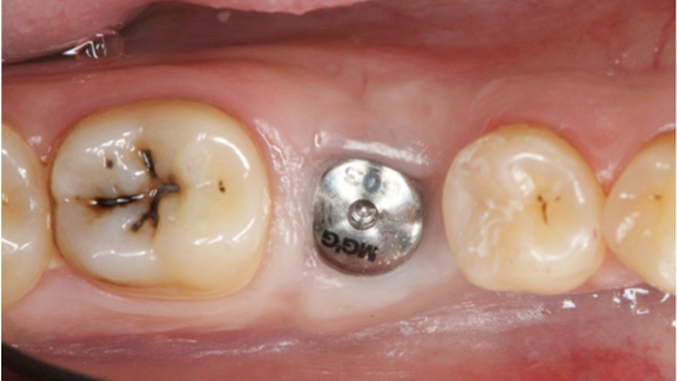

Clinical case: # 46 implant placement & GBR using i-Gen membrane for significant vertical resorption & mixed bone defect

- Courtesy of Dr. Iulian Filipov, Romania -

AnyRidge, mandibular posterior, i-Gen, resorption, bone defect, bone regeneration, space management, #46, GBR, Dr. Iulian Filipov

AnyRidge implant system, i-Gen